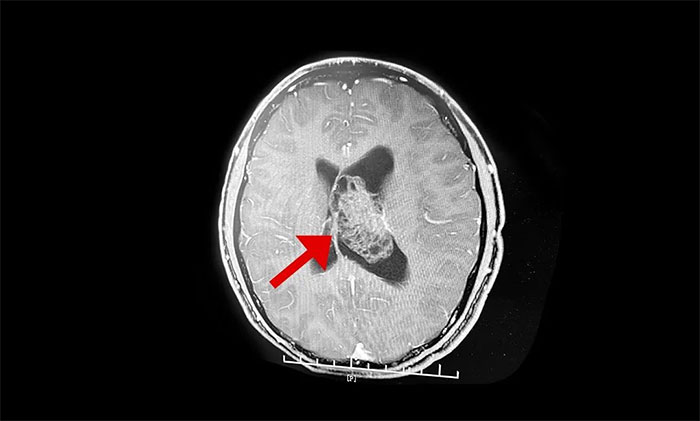

最终被诊断为中枢神经细胞瘤。中枢神经细胞瘤属于比较罕见的脑肿瘤,一般直径超过三公分即为巨大肿瘤,而李威脑室内的肿瘤直径竟达七公分,接近一个拳头大小。幸运的是,顺利手术切除。

上海蓝十字脑科医院神经外科李士其教授介绍,中枢神经细胞瘤(Central neurocytoma,CN)是少见的神经系统肿瘤,1982年由Hansson首次报道并命名,2016年WHO神经系统肿瘤组织学分类将其归类为神经元和混合型神经元胶质瘤(WHOⅡ级)。中枢神经细胞瘤仅占颅内肿瘤的0.25%~0.50%,好发于20~40岁青年人,无性别差异。病史一般较长,可达数十年之久,好发于侧脑室透明隔,当病变累及Monro孔时,阻塞脑脊液循环,引起头痛、头晕、恶性、呕吐以及不同程度视力改变等非特异性颅内高压症状。

▲ 非典型性中枢神经细胞瘤